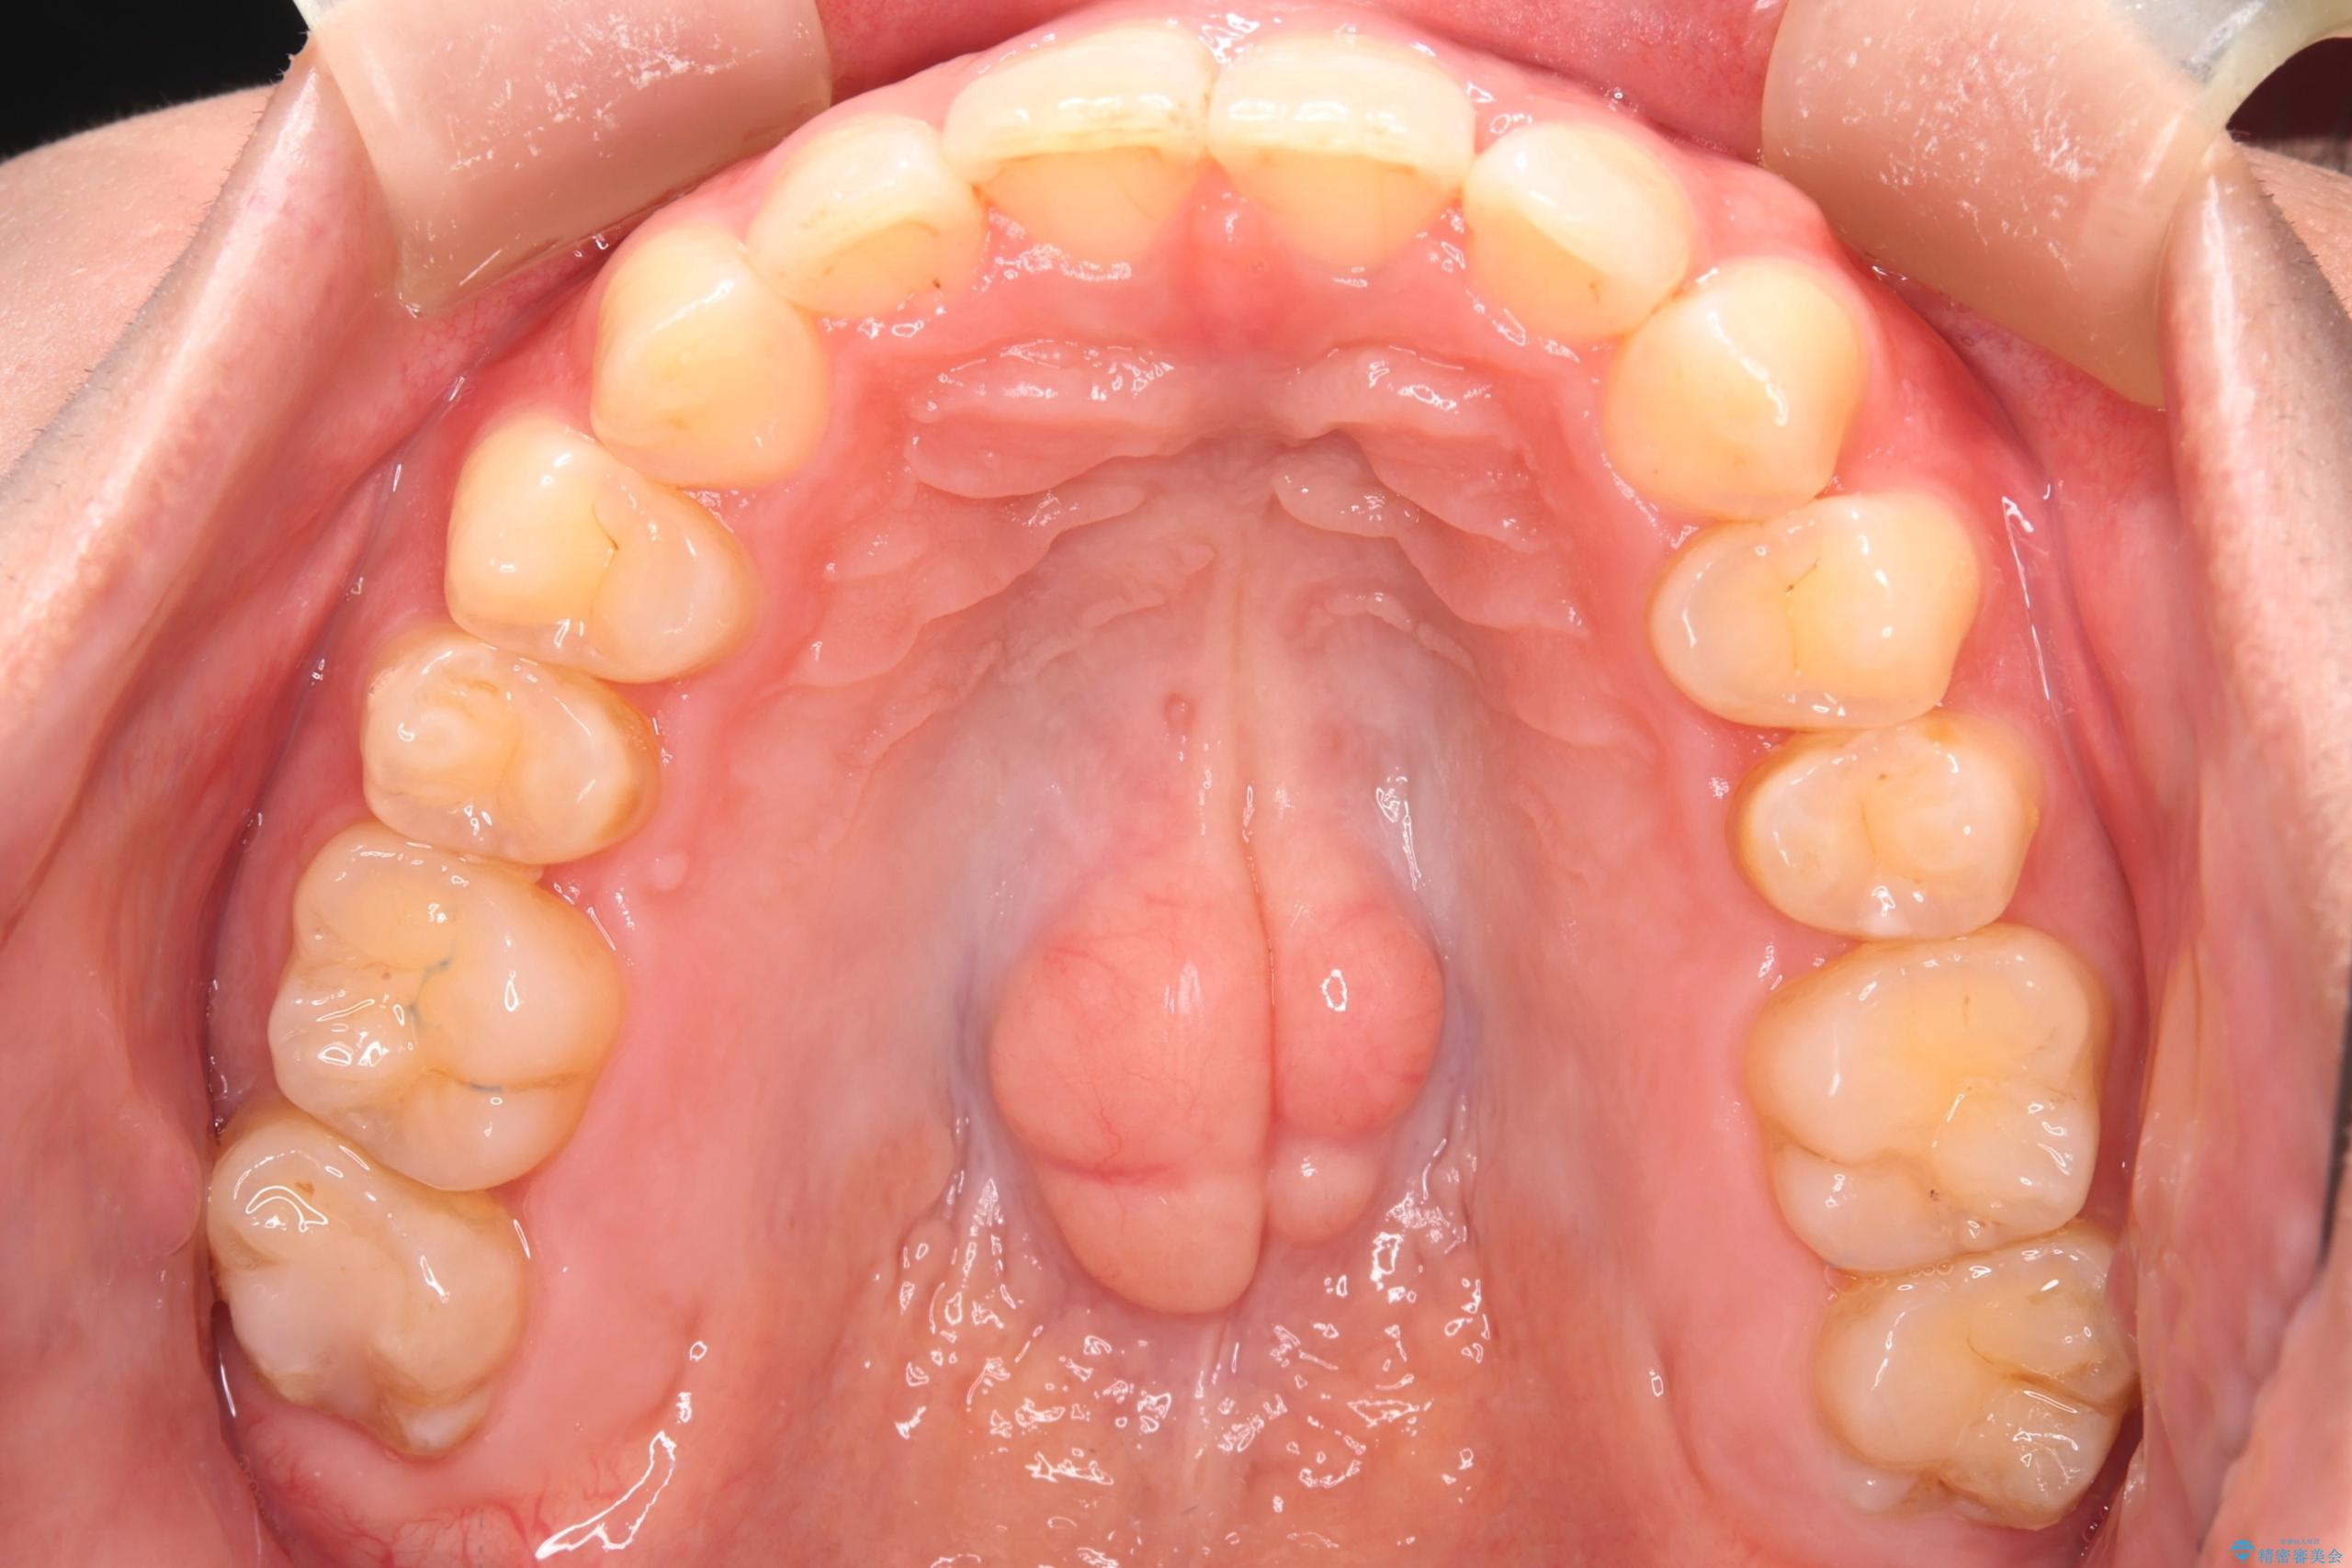

- 下の歯のがたつきを主訴に来院されました。

下の歯のがたつきと右の奥歯の噛みあわせ改善するために治療計画を立てることにしました。

下の前歯のがたつき改善にはIPR(歯と歯の間を削る処置)を行いました。